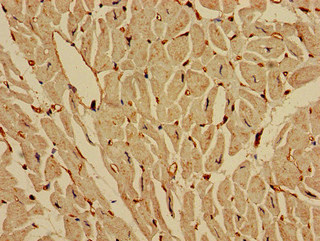

圖片:

應用范圍:ELISA, IHC

Application Recommended Dilution IHC 1:20-1:200 -